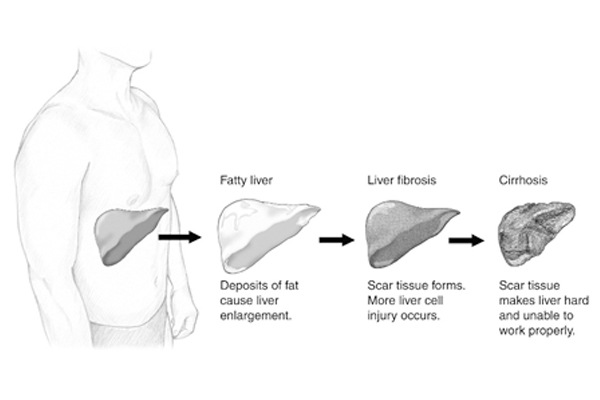

Non-Alcoholic Fatty Liver Disease is increasingly common worldwide and linked to obesity, diabetes, and metabolic syndrome. Recent research underscores that MASLD treatment centers on lifestyle modification and drug therapies targeted at metabolic risk factors.